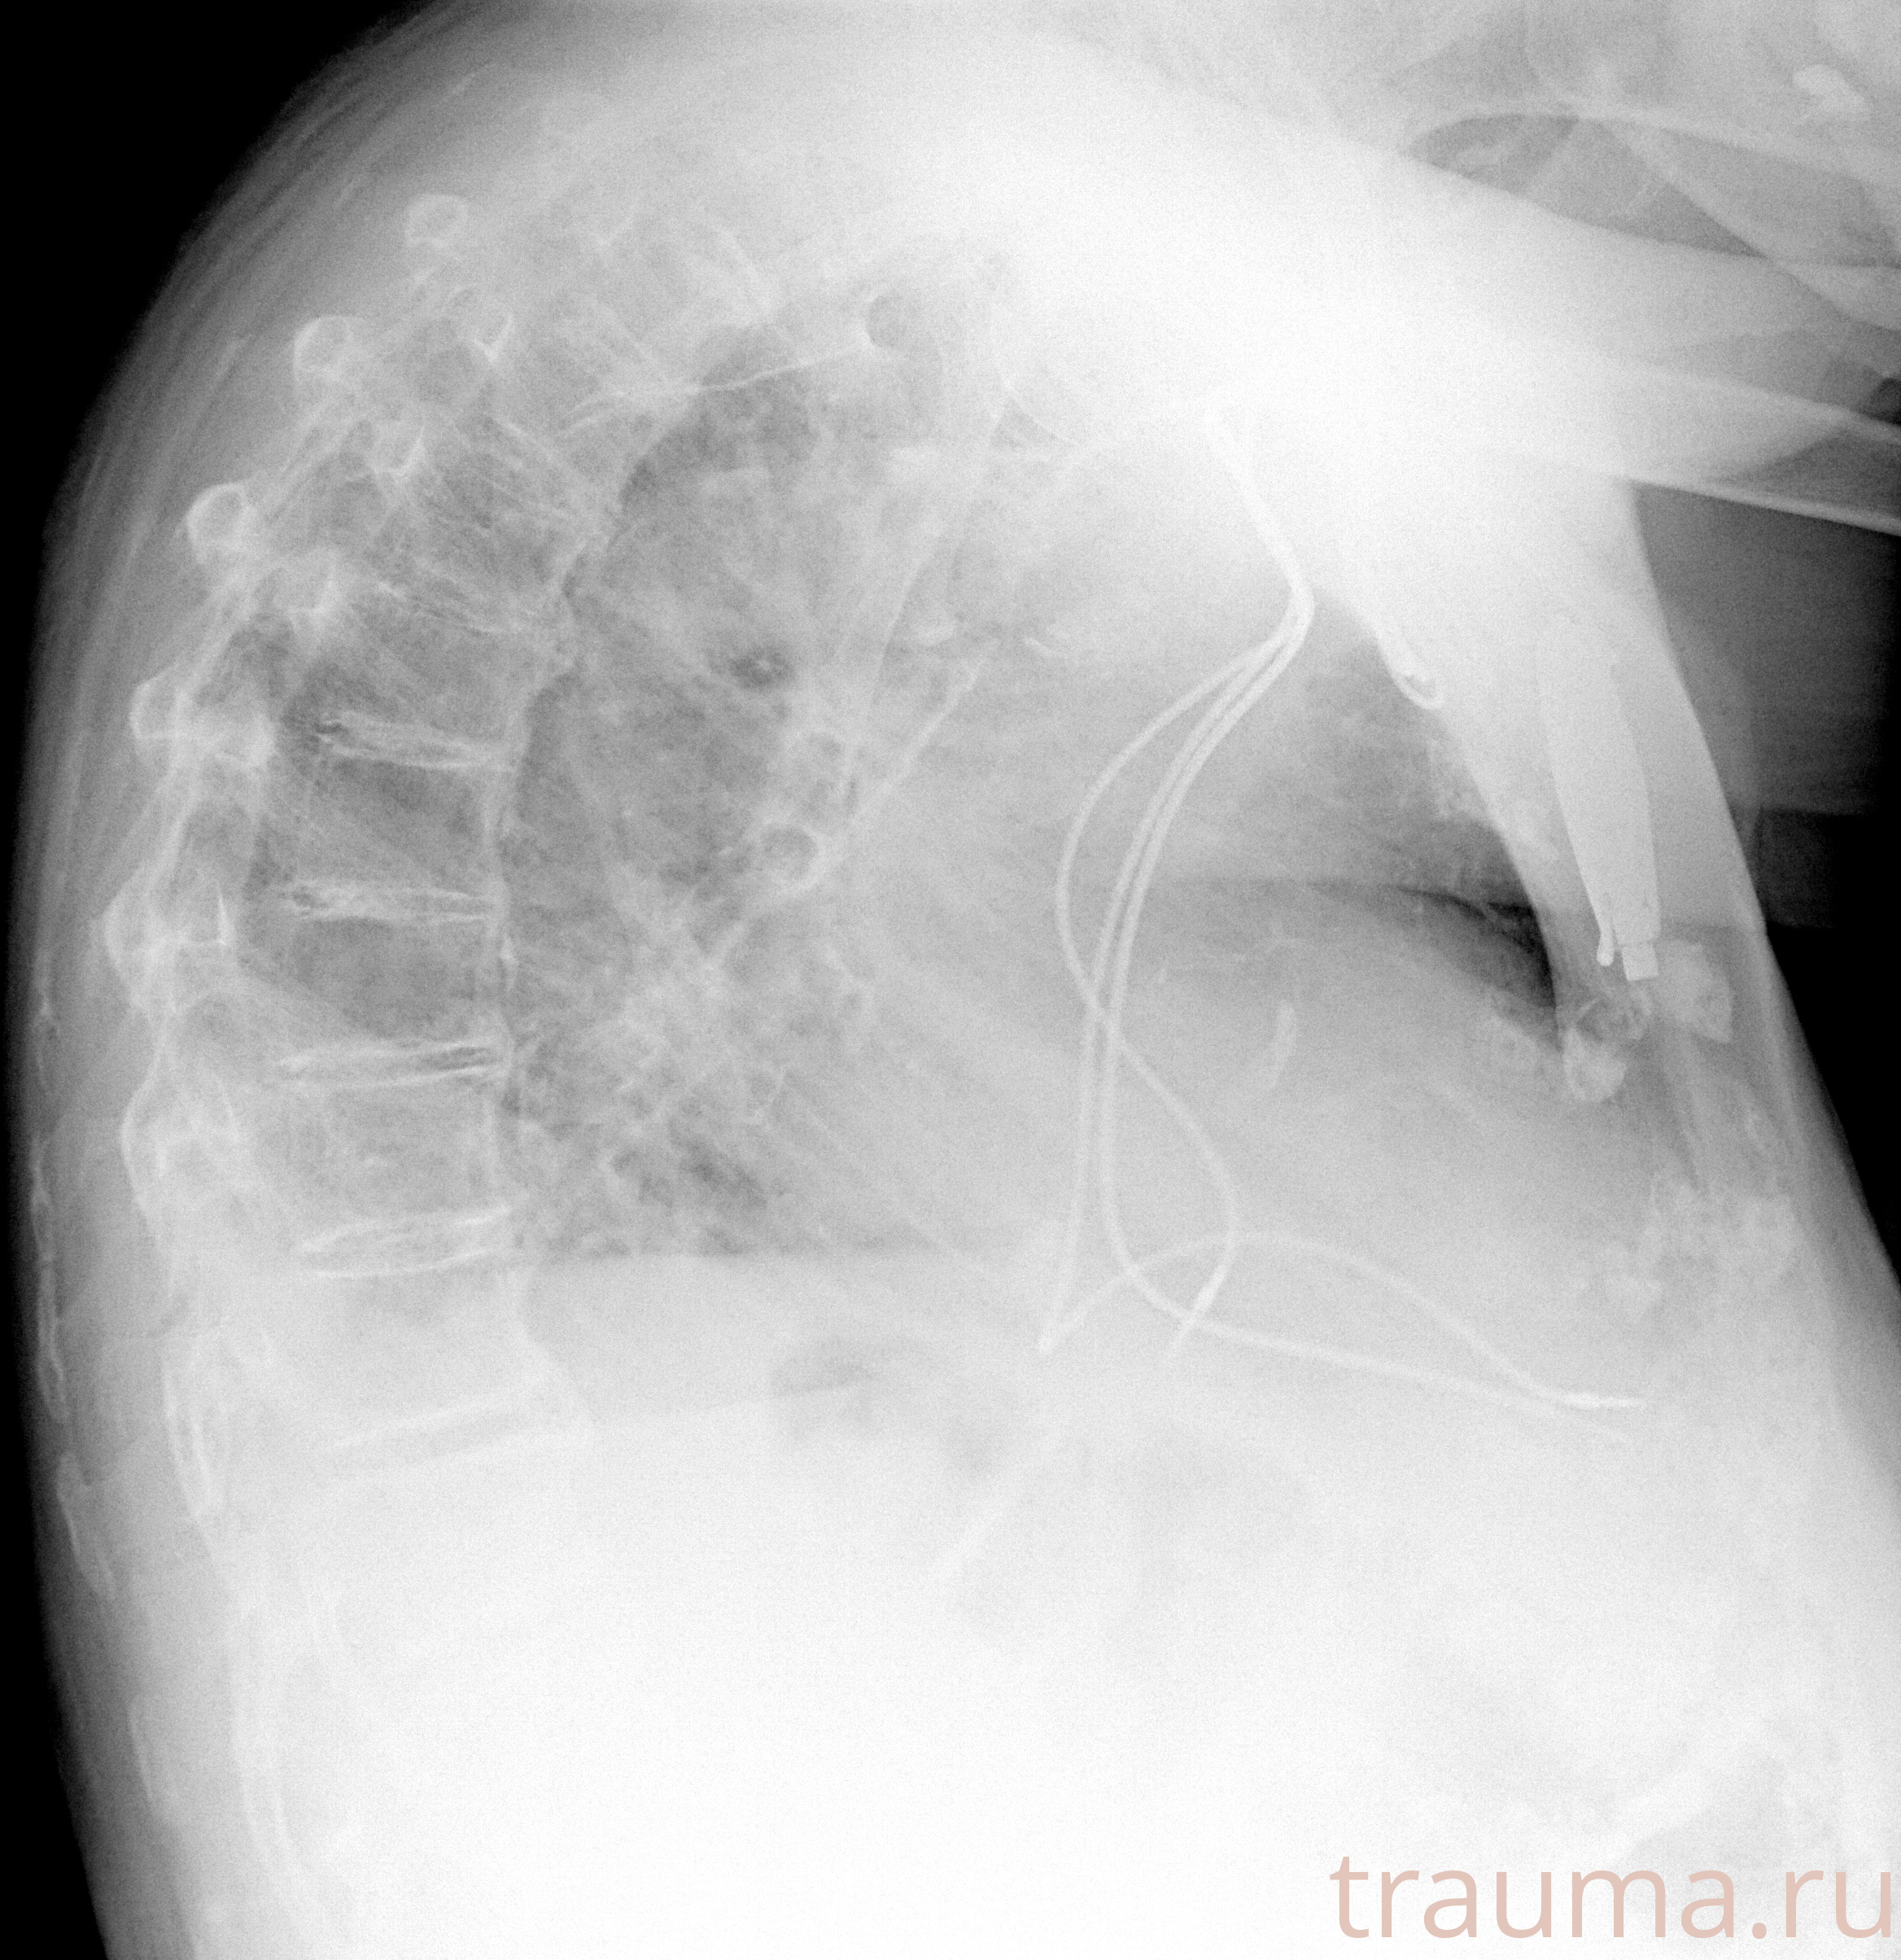

Рентгенограммы

Рентген на дому: по вашему адресу приезжает врач-рентгенолог, травматолог-ортопед с мобильным рентгеновским аппаратом, проводит диагностику травмы или заболевания, делает необходимые рентгенограммы, дает рекомендации по дальнейшему лечению. Получить качественные снимки в домашних условиях возможно благодаря уникальной методике, разработанной МосРентген Центром для института  Склифосовского

при переломе шейки бедра и пневмонии от компании МосРентген Центр - партнера Института имени Склифосовского